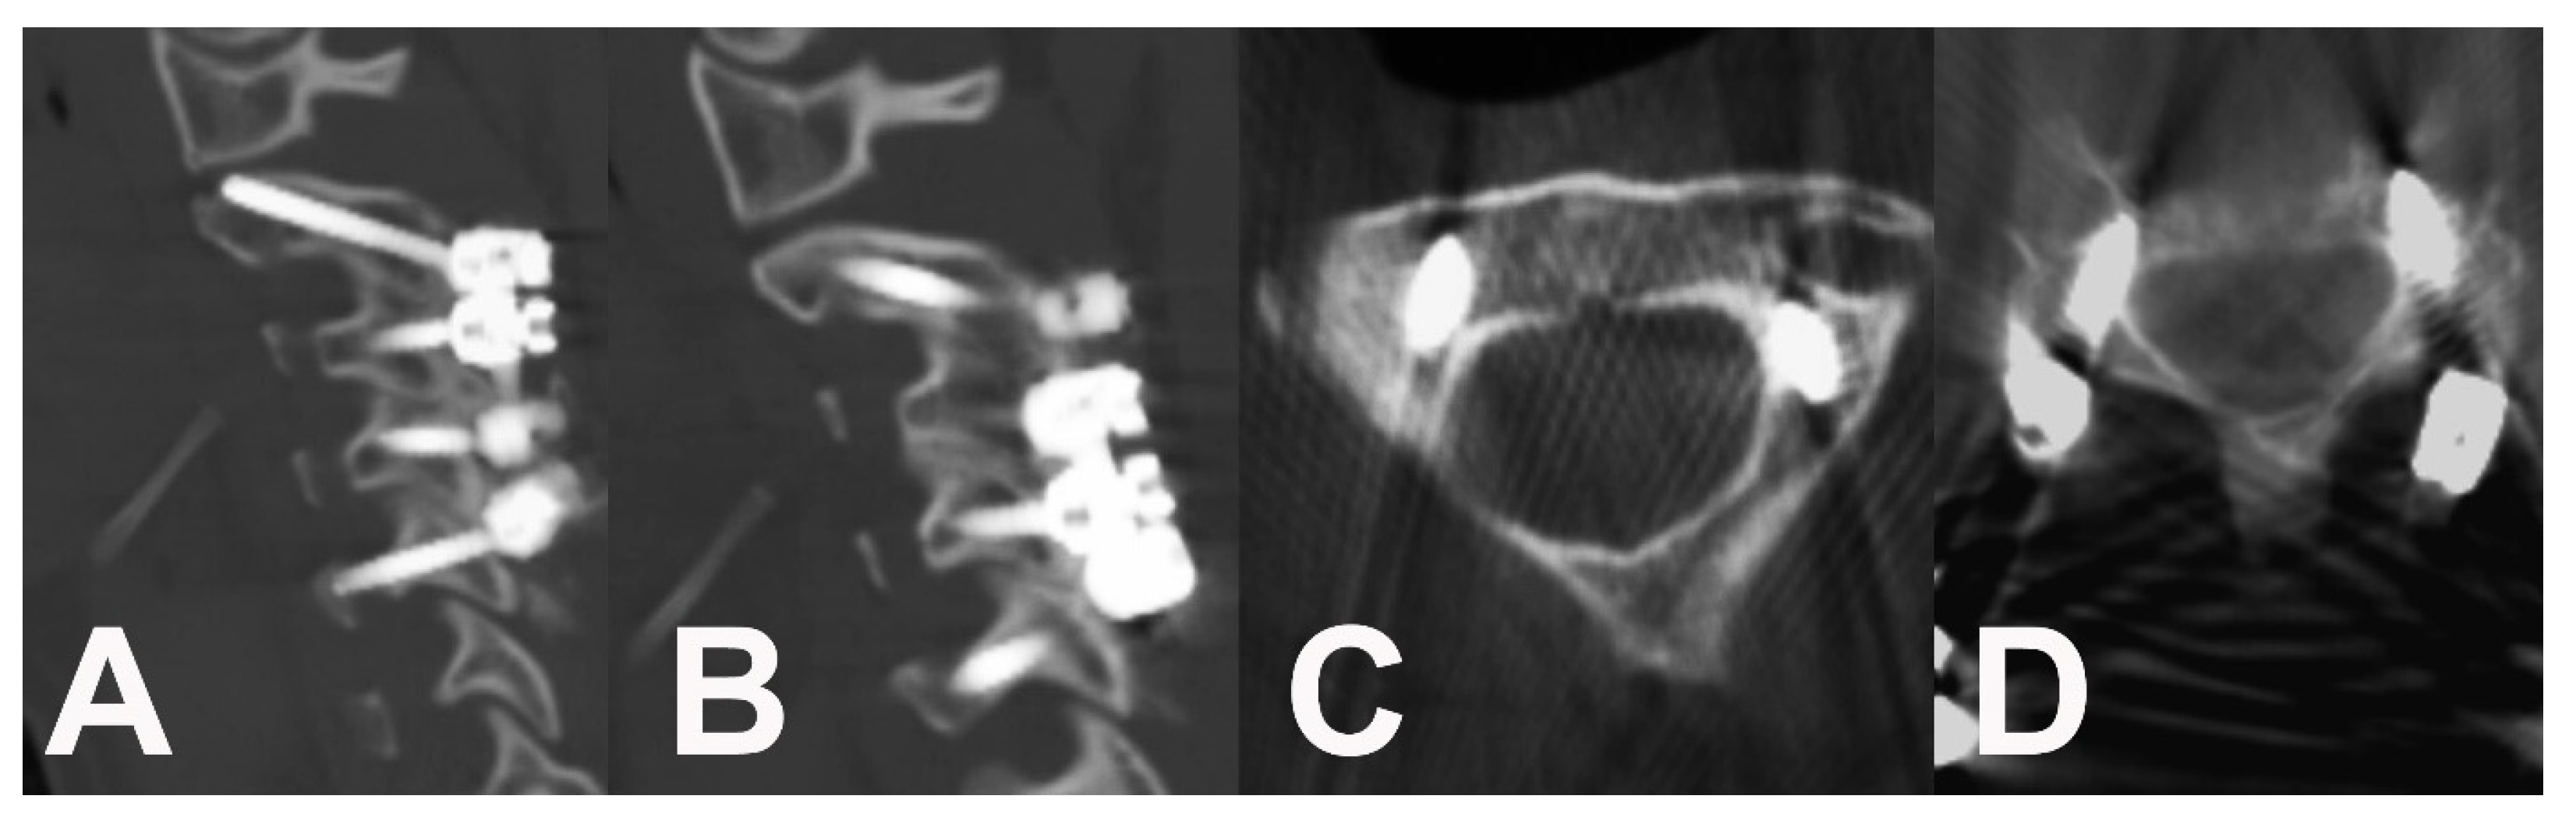

2. Case Report